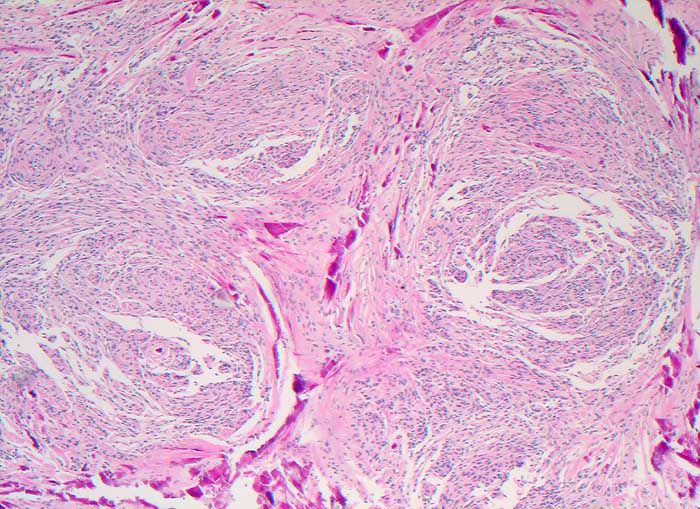

Meningeom

benigner Tumor

Rückenmark

Deutliche Wirbelbildungen und ausgedehnte Verkalkungen

Spinaler Tumor Th 12.

Am ehesten handelt es sich um einen transitionalen Typ mit häufigem Nachweis von Wirbelbildungen und Psammomkörperchen.

Histologie

50